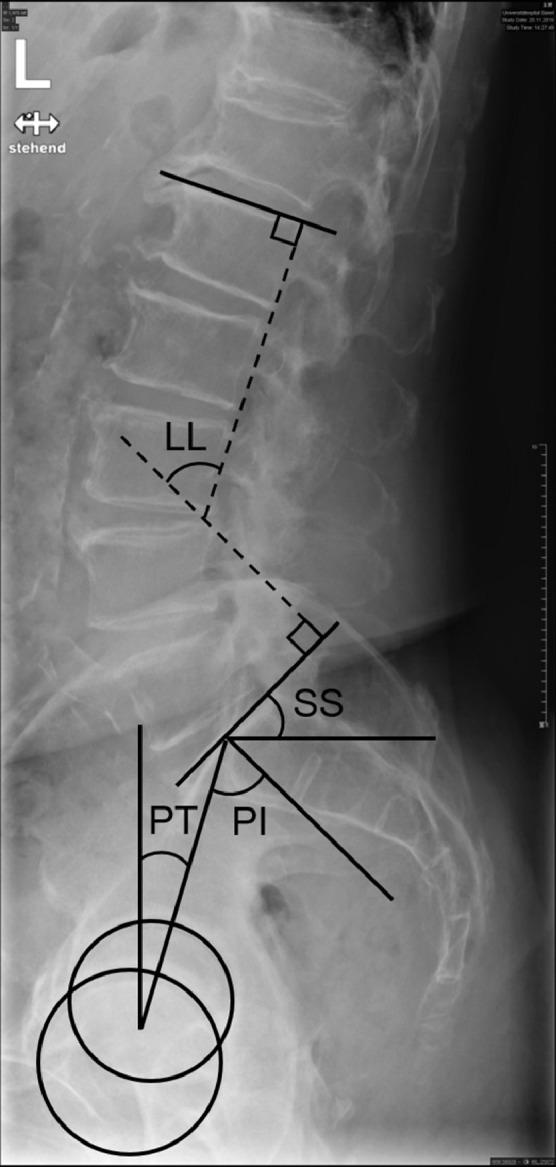

Age and body mass index (BMI) were extracted. Fatty infiltration was rated according to Goutallier classification and the severity of LSS was graded according to Schizas at five intervertebral disc levels. Overall fatty infiltration was computed as average fatty infiltration (aFI) and severity of LSS was defined as the highest severity of LSS of all segments. The sagittal spinopelvic parameters pelvic incidence (PI), pelvic tilt (PT), sacral slope (SS), lumbar lordosis (LL) and PI-LL were measured. Associations among parameters were assessed using Spearman correlation coefficients adjusted for age (α = 0.05).

提取年龄和体重指数(BMI)。根据Goutallier分类对脂肪浸润进行评分,并根据Schizas方法在五个椎间盘水平对LSS的严重程度进行分级。总体脂肪浸润计算为平均脂肪浸润(aFI),LSS的严重程度定义为所有节段中LSS的最高严重程度。测量矢状面脊柱-骨盆参数骨盆入射角(PI)、骨盆倾斜角(PT)、骶骨倾斜角(SS)、腰椎前凸角(LL)和PI-LL。使用经年龄调整的Spearman相关系数评估参数之间的关联(α = 0.05)。